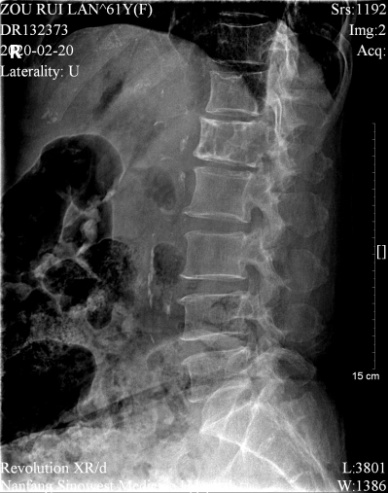

邹阿姨术前影像资料

邹阿姨入院后,骨伤科黄刚主任对其进行了仔细检查。腰椎CT显示腰1椎体及左侧有肿物,腹膜后及盆腔多发肿大淋巴结,腰椎骨质增生。

胸腰椎MRI发现胸10/11黄韧带肥厚、钙化,硬脊膜受压,椎管严重狭窄。PET-CT检查显示腰1椎体及左侧附件溶骨性破坏,伴代谢增高,考虑为骨原发恶性肿瘤。局麻腰椎穿刺活检考虑孤立性浆细胞瘤。